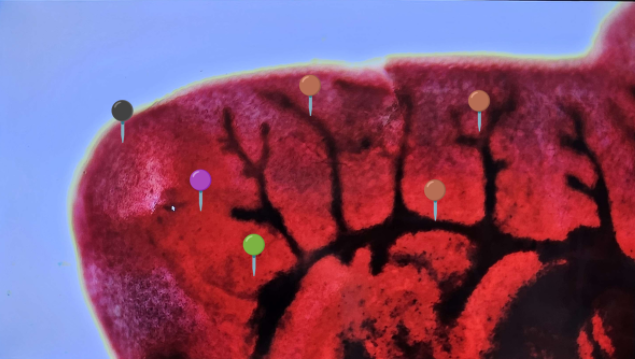

🦋 Fasciola hepatica (Postać dojrzała)

🧩🦠 Organelle:

⚫️ - przyssawka gębowa;

🟣 - gardziel;

🟢 - przełyk;

🟤 - jelito i rozgałęzienia;

🟡 - przyssawka brzuszna;

🔵 - macica z jajami.

😷❓ Parazytoza: Fascjoloza